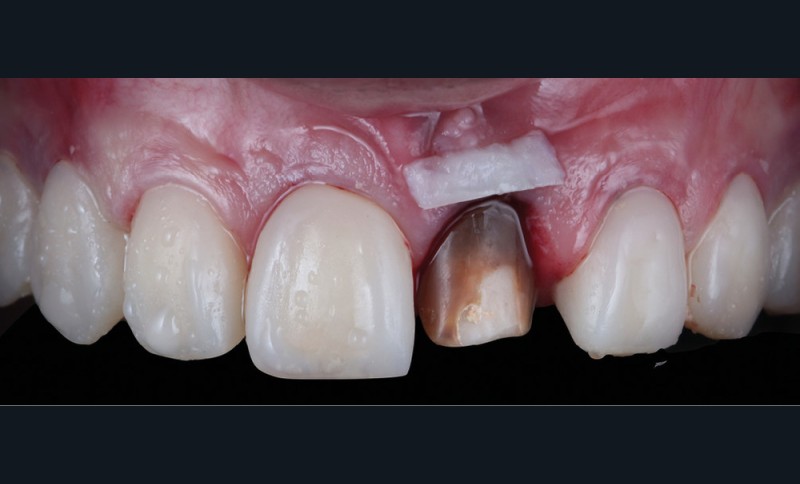

Acte 4 : préparation dentaire et gestion du rose additive (fig. 5 et 6)

À trois mois, les tissus en cours de cicatrisation se stabilisent ; nous passons à la préparation des dents [3].

Au vu des larges plages de cément exposées, nous optons pour une préparation de type couronne sur 53, 11, 21 et 23, afin de privilégier un assemblage prothétique de type scellement. Pour 15, 14, 24 et 25, nous resterons essentiellement dans l’émail et en vestibulaire. Ce choix nous oriente sur une préparation de type facette dont l’assemblage prothétique se fera par collage.

Nous observons que les tissus mous autour de la dent dyschromiée 21 se sont affinés et laissent transparaître le substrat radiculaire [4]. Un épaississement des tissus mous à l’aide d’une greffe de conjonctif s’impose. Dernières retouches également pour la ligne des collets par de petites gingivectomies au bistouri électrique. Des couronnes provisoires, basées sur le nouveau profil d’émergence, sont ensuite posées afin d’obtenir une cicatrisation guidée.